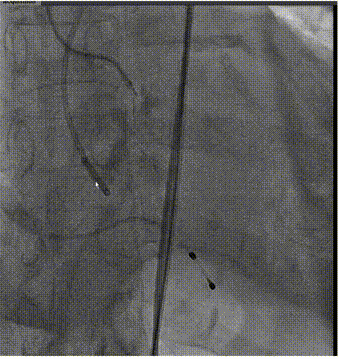

手术过程概览

主动脉根部造影

导丝跨瓣

球囊预扩

输送器过弓

输送器定位

瓣膜定位

瓣膜脱钩

全息剪影